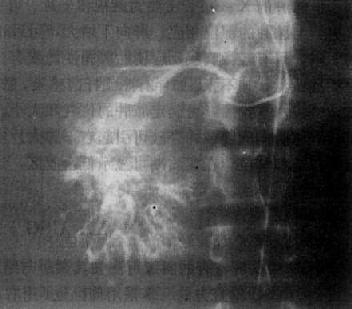

图4-3-1 原发性肝癌动脉造影

肝动脉造影显示肝内一团巨块状肿瘤血管,大小不均,形态不规则,

其中心呈湖样充盈。供血动脉增粗、迂曲

选择性肝动脉影是诊断肝癌的有效方法,它能查出直径小至2cm的肝癌,并确定其范围与数目,供血是否丰富,还可了解有无肝硬化和附近有无肿瘤转移。肝癌的动脉造影可有以下表现:①显示肿瘤血管,表现为肿瘤区内大小不均、形状不规则的血管影或呈“湖样”充盈,其供血动脉增粗;②动脉拉直和移位,动脉边缘不规则且僵硬,系因肿瘤包绕所致;③毛细血管期可见肿瘤染色,呈高密度的结节影;④肝实质期显示为充盈缺损区;⑤有时可形成动静脉瘘,使相邻的门静脉分支早期显影(图4-3-1)。